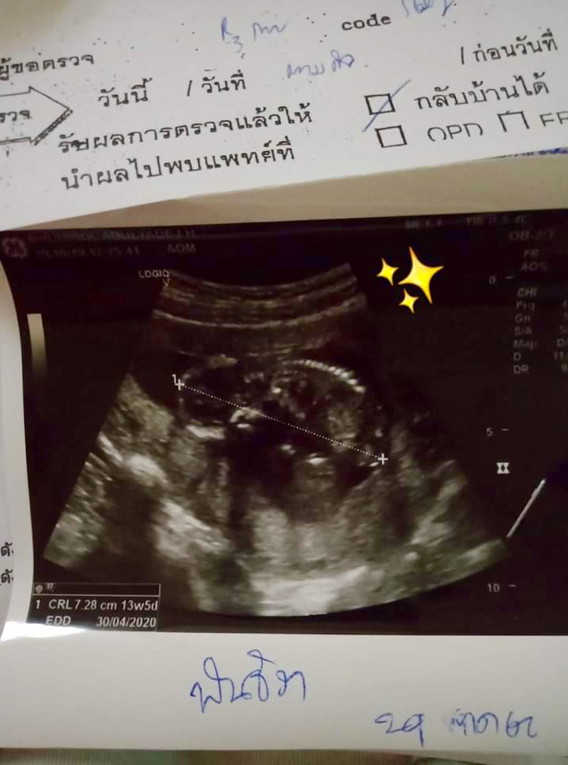

ตอนนั้นซาว 13+5 ค่ะ ตอนนี้ 19+5 แล้วค่ะ